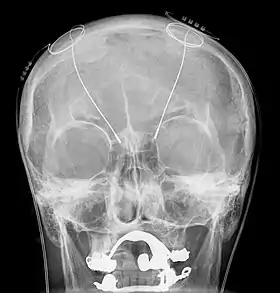

Lateral X-ray of the head: Deep brain stimulation in Obsessive–compulsive disorder (OCD). 42-year-old man, surgery in 2013.

DBS has been used in a small number of clinical trials to treat people with severe treatment-resistant depression (TRD).[43] A number of neuroanatomical targets have been used for DBS for TRD including the subgenual cingulate gyrus, posterior gyrus rectus,[44] nucleus accumbens,[45] ventral capsule/ventral striatum, inferior thalamic peduncle, and the lateral habenula.[43] A recently proposed target of DBS intervention in depression is the superolateral branch of the medial forebrain bundle; its stimulation lead to surprisingly rapid antidepressant effects.[46]

The small numbers in the early trials of DBS for TRD currently limit the selection of an optimal neuroanatomical target.[43] Evidence is insufficient to support DBS as a therapeutic modality for depression; however, the procedure may be an effective treatment modality in the future.[47] In fact, beneficial results have been documented in the neurosurgical literature, including a few instances in which people who were deeply depressed were provided with portable stimulators for self-treatment.[48][49][50]

A systematic review of DBS for TRD and OCD identified 23 cases, nine for OCD, seven for TRD, and one for both. "[A]bout half the patients did show dramatic improvement" and adverse events were "generally trivial" given the younger age of the psychiatric population relative to the age of people with movement disorders.[51] The first randomized, controlled study of DBS for the treatment of TRD targeting the ventral capsule/ventral striatum area did not demonstrate a significant difference in response rates between the active and sham groups at the end of a 16-week study.[52] However, a second randomized controlled study of ventral capsule DBS for TRD did demonstrate a significant difference in response rates between active DBS (44% responders) and sham DBS (0% responders).[53] Efficacy of DBS is established for OCD, with on average 60% responders in severely ill and treatment-resistant patients.[54] Based on these results the Food and Drug Administration (FDA) has approved DBS for treatment-resistant OCD under a Humanitarian Device Exemption (HDE), requiring that the procedure be performed only in a hospital with specialist qualifications to do so.